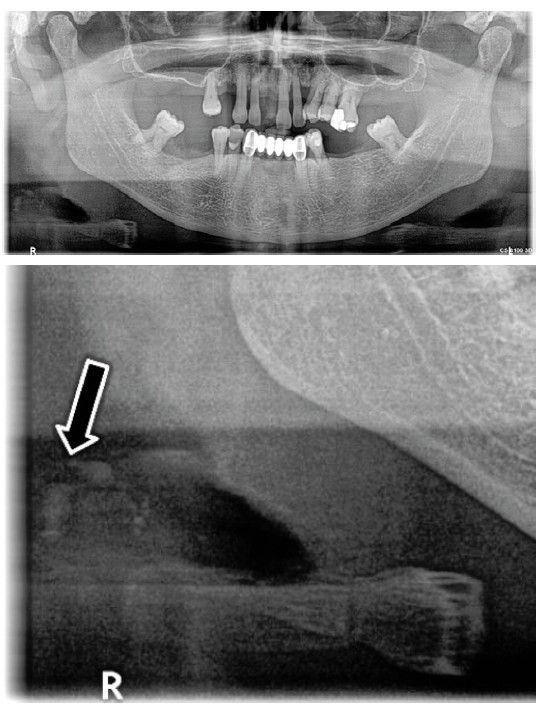

Estas calcificaciones que, generalmente se localizan en la bifurcación carotídea, se presentan como masas radiopacas en la región de la radiografía panorámica correspondiente a los tejidos blandos del cuello, en una zona aproximada entre las vértebras cervicales C2, C3 y C4, a una distancia aproximada entre 1 y 4 cm posteroinferior al ángulo mandibular13. Pueden variar en tamaño y forma, siendo lineales verticales, nodulares o heterogéneas, y pueden presentarse de manera unilateral o bilateral, así como ser únicas o múltiples13-15.

El objetivo de esta publicación es contribuir a la prevención de los problemas cerebrovasculares desde la clínica dental, mediante la presentación de tres casos clínicos en los que se detectaron de manera casual calcificaciones carotídeas durante un examen radiográfico de control, realizado mediante una radiografía panorámica, en pacientes con patologías periodontales en fase de mantenimiento.